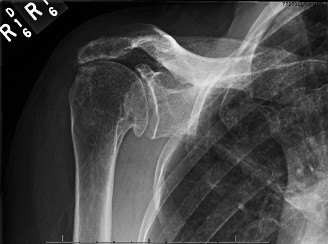

Computed Tomography (CT) Scan:

Given the advanced changes on plain radiographs and the consideration for reverse total shoulder arthroplasty (RTSA), a dedicated CT scan of the glenoid was obtained to precisely assess glenoid bone stock, morphology, and retroversion.

* Glenoid Morphology: Revealed severe superior and posterior glenoid erosion with significant eccentric wear, resulting in a B2 or C-type glenoid according to the Walch classification, characterized by severe posterior erosion and retroversion. The erosion compromised a significant portion of the superior and posterior glenoid bone stock, necessitating careful preoperative planning for glenoid baseplate fixation and potential bone grafting.

* Humeral Head: Confirmed severe degenerative changes and cystic lesions.

* Interpretation of the provided image: This image appears to be a post-operative AP X-ray of a shoulder following Reverse Total Shoulder Arthroplasty (RTSA). We can clearly see the components: a humeral stem with a polyethylene cup and a glenosphere affixed to the glenoid, superiorly offset and slightly inferiorly positioned. This image is crucial for demonstrating the definitive surgical treatment for Rotator Cuff Arthropathy.

Surgical Indication:

Given the patient's symptomatic Hamada Grade 4A RCA, severe pseudoparalysis, and failure of comprehensive non-operative treatment, the gold standard surgical intervention is Reverse Total Shoulder Arthroplasty (RTSA). RTSA fundamentally alters the biomechanics of the shoulder, moving the center of rotation medially and inferiorly. This change allows the deltoid muscle, which is typically preserved in RCA, to become the primary elevator and abductor of the arm, compensating for the deficient rotator cuff.